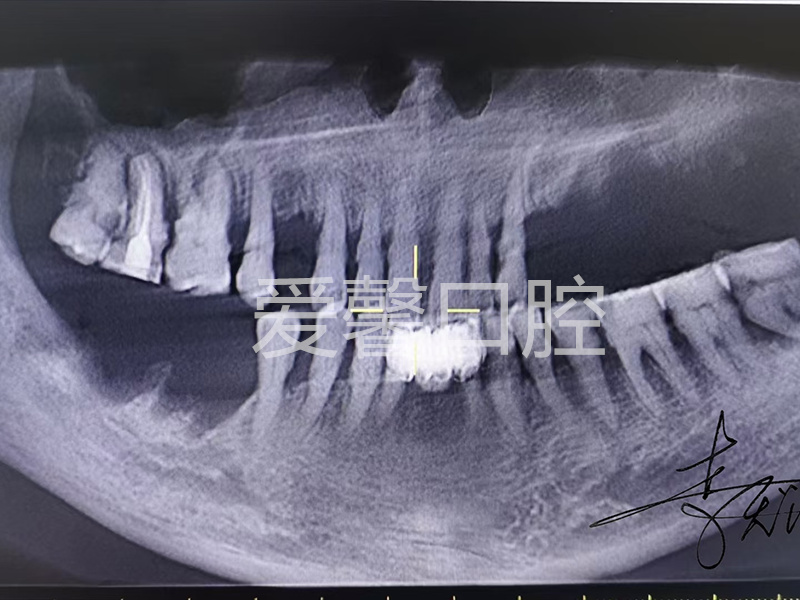

案例展示